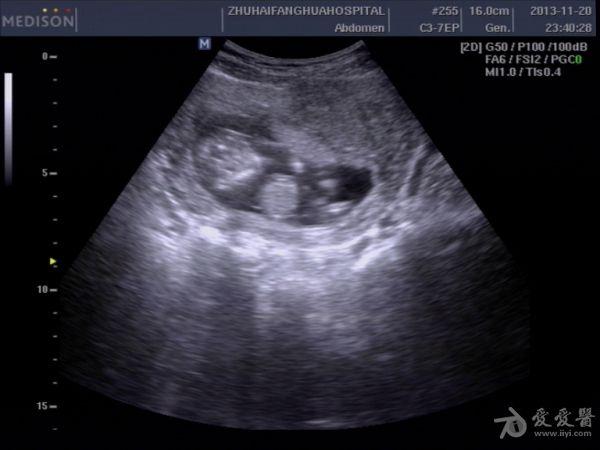

13周孕,24岁,初孕 因腹痛急诊***检查,是当天早上3点钟,医生提的黑白超,学生胆挺大的,超声图像如下:

学生直接诊断胎儿内脏外翻,上班后复查图像觉得问题不大,但还是被学生的胆大吓了一跳。这孩子连孕妇的联系方式都没留,人就放走了,今天终于联系上了孕妇,结果在市产院做的引产,结果同上。学生对我说,本来想诊断脐膨出的,觉得不像,还是像内脏外翻多些,大家说说,这孩子是该批评呢,还是该鼓励。我都有点哭笑不得了。